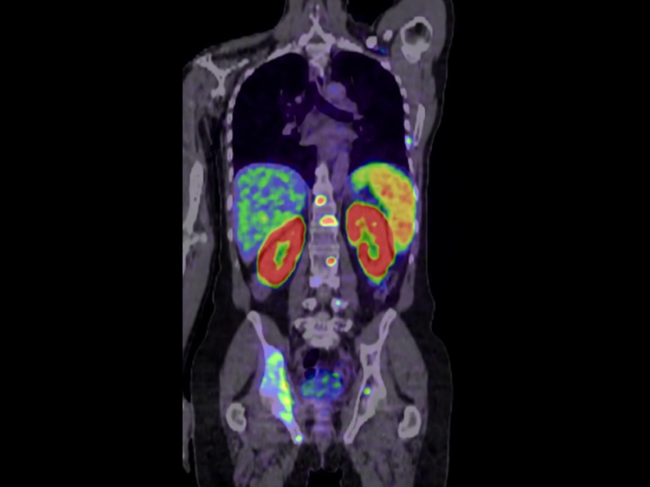

PET image of torso

FDA approves Telix’s radiopharmaceutical prostate cancer imaging agent Illuccix

PERTH, Australia – The FDA has given the green light to Telix Pharmaceuticals Ltd.’s lead radiopharmaceutical imaging agent, Illuccix, for prostate cancer. Illuccix is a kit for the preparation of gallium-68 (68Ga) prostate-specific membrane antigen (PSMA) 11 for imaging prostate cancer with positron emission tomography (PET). It targets PSMA, a protein that is overexpressed on the surface of more than 90% of primary and metastatic prostate cancer cells. Read More